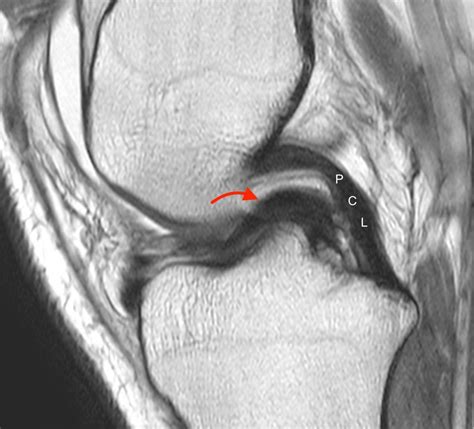

• Magnetic Resonance Imaging (MRI) to provide detailed images of the meniscus and surrounding structures. MRI is particularly useful in identifying the location and extent of the tear.

In some cases, an arthroscopy may be performed to directly visualize the meniscus and confirm the diagnosis. This minimally invasive procedure involves inserting a small camera into the knee joint through a tiny incision.